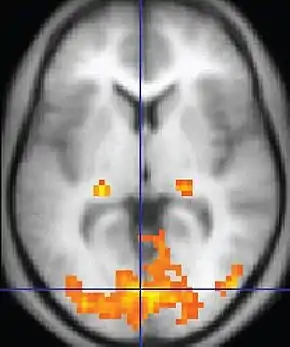

| Functional MRI (fMRI) | Blood-oxygen-level dependent imaging | BOLD | Changes in oxygen saturation-dependent magnetism of hemoglobin reflects tissue activity.[29] | Localizing brain activity from performing an assigned task (e.g. talking, moving fingers) before surgery, also used in research of cognition.[30] | ![]() |

Functional MRI (fMRI) measures signal changes in the brain that are due to changing neural activity. It is used to understand how different parts of the brain respond to external stimuli or passive activity in a resting state, and has applications in behavioral and cognitive research, and in planning neurosurgery of eloquent brain areas.[48][49] Researchers use statistical methods to construct a 3-D parametric map of the brain indicating the regions of the cortex that demonstrate a significant change in activity in response to the task. Compared to anatomical T1W imaging, the brain is scanned at lower spatial resolution but at a higher temporal resolution (typically once every 2–3 seconds). Increases in neural activity cause changes in the MR signal via T*

2 changes;[50] this mechanism is referred to as the BOLD (blood-oxygen-level dependent) effect. Increased neural activity causes an increased demand for oxygen, and the vascular system actually overcompensates for this, increasing the amount of oxygenated hemoglobin relative to deoxygenated hemoglobin. Because deoxygenated hemoglobin attenuates the MR signal, the vascular response leads to a signal increase that is related to the neural activity. The precise nature of the relationship between neural activity and the BOLD signal is a subject of current research. The BOLD effect also allows for the generation of high resolution 3D maps of the venous vasculature within neural tissue.